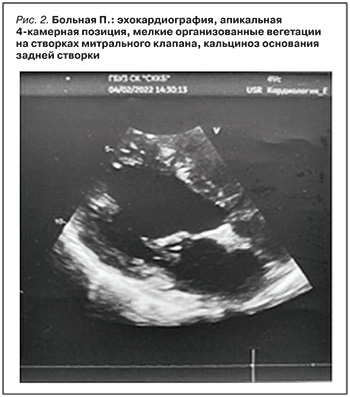

ЭхоКГ с допплер-анализом: дилатация всех полостей сердца. Миокард ЛЖ, межжелудочковой перегородки неоднородной эхоструктуры с участками повышенной эхогенности. Гипертрофия миокарда межжелудочковой перегородки. Створки митрального клапана изменены, фиброз створок и подклапанных структур, склеротические изменения левого атриовентрикулярного кольца, кальциноз основания задней створки митрального клапана, трикуспидального клапана, мелкие организованные вегетации на створках митрального клапана (рис. 2). Недостаточность митрального (2 ст.) и трикуспидального (2 ст.) клапанов. Склеротические изменения стенок аорты и аортальных клапанов, недостаточность аортального клапана (2 ст.), наличие организованных вегетаций на створках аортального клапана. Дисфункция клапана легочной артерии. Легочная гипертензия (СДЛА 54 мм рт.ст.).

ФВ ЛЖ – 73%. Диастолическая дисфункция левого желудочка.